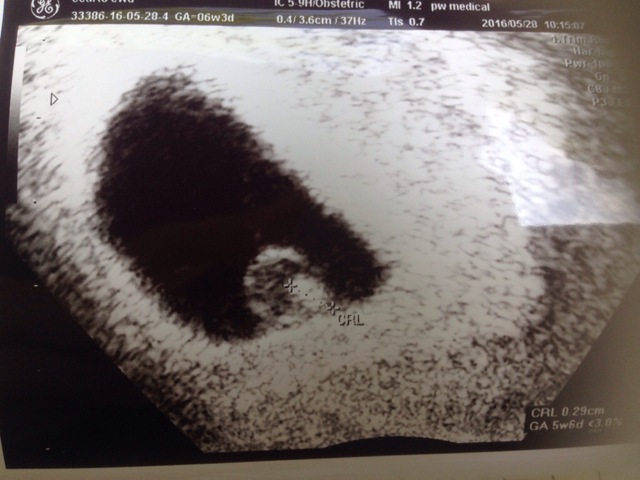

Wczoraj bylam wlasnie prywatnie w Hadze na USG u polskiej ginekolog i powiem Ci, ze warto bylo!!!

Wiem, ze wszystko jest super, widzialam i slyszalam serduszko :)

Jak chcesz prywatnie to idz jak ja, w 7 (a dokladniej 6tc+3 miala USG) tygodniu, zobaczysz fasolinke i prawdopodobnie juz serduszko. Wczesniej bym nie szla bo szkoda wydac 150 euro by nic nie zobaczyc.